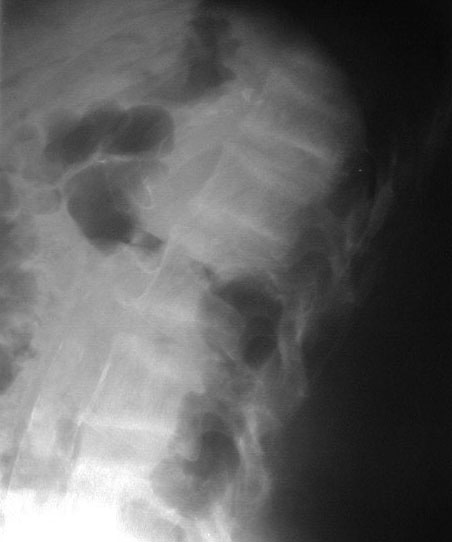

SIGNO DE LA DOBLE LÍNEA

Otro ejemplo en un paciente con infartos óseos múltiples en fémur distal y tibia proximal.